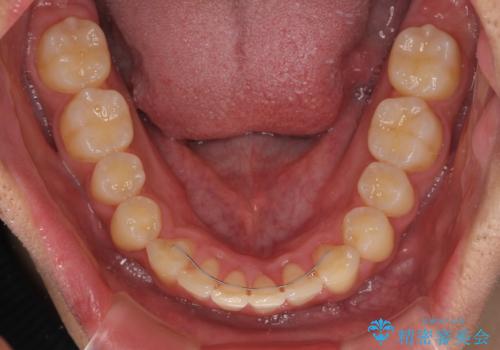

- 上下前歯のデコボコと、それに伴う出っ歯を気にして来院された患者様です。

インビザラインによる上下歯列の側方拡大と後方移動、IPR(歯と歯の間を削る)にるスペースの獲得により歯列を整えることとしました。

歯と歯の間を削ることでうまくスペースコントロールでき、また、毎日22時間以上しっかりとマウスピースを装着していただいたので、スムーズに治療が進みました。

治療途中で転勤となり、遠方からの通院となったため、来院間隔空いてしまいましたが、2年間で終えることができました。